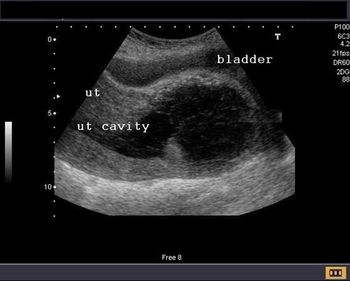

At 34 weeks’ gestation, a pregnant woman underwent a routine ultrasound examination. The findings revealed an unusual anomaly. Can you identify it?